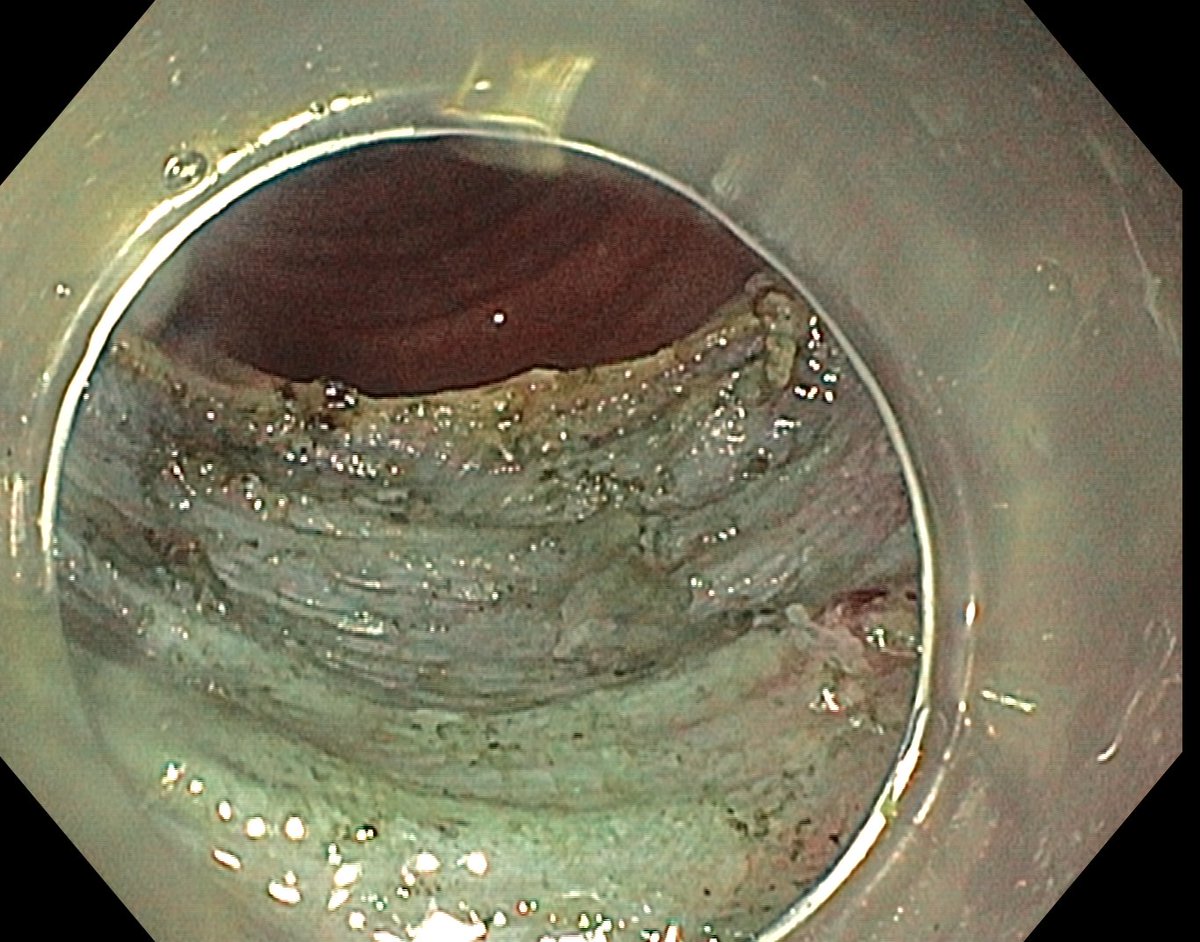

📢 March 2026 Issue #ACGCRJ 📷: Endoloop assisted hot snare polypectomy of a large brunner gland hamartoma in distal duodenum using colonoscope.🔦 🔗journals.lww.com/acgcr/pages/cu… @DushDahiya @DaniyalAbbasMD @AmCollegeGastro